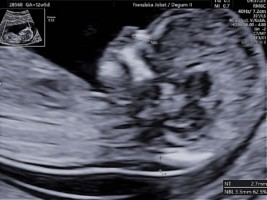

Ultraschalldiagnostik 12-14. SSW Erst-Trimesterscreening (NT-Mesung):

Das Ersttrimesterscreening ist eine differenzierte Ultraschalldiagnostik in der 12-14 SSW die ein ausführliches Organscreening und die Erfassung von sonografischen Chromosomenmarken, sowie eine Risikoberechnung aus Laborparamentern und Ultraschallmarkern beinhaltet. Diese Untersuchung ist keine Leistung der Krankenkassen und kann nur als IGEL-Leistung wahrgenommen werden

Mit Hilfe des Ersttrimesterscreenings (ETS) ist schon in der 12.-14. SSW durch die Beurteilung der Nackenfalte , des Nasenbeins und weiterer sonographischer Parameter (Ductus venosus, Trikuspidalklappe am Herzen etc.) sowie einer Blutentnahme (PAPP-A und freies ß HCG= plazentare Hormone) eine Risikoanalyse für das wahrscheinliche Auftreten einer Chromosomenstörungen Trisomie 21, Trisomie 13 oder Trisomie18 möglich. Die Erkennungsrate der Untersuchung beträgt ca.90-95% mit einer Falsch-Positiv-Rate von 2,5-5%.